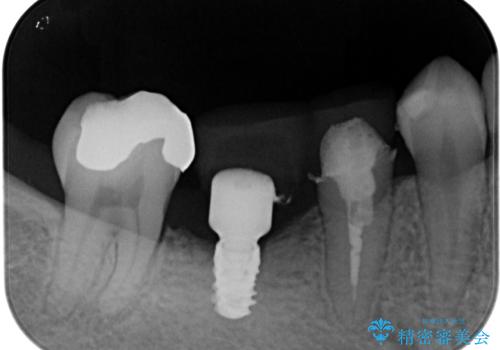

- インレーブリッジをインプラントにやり替えて銀歯を白くしたいとのことで来院された患者様です。

既に抜歯をして歯のない箇所にはインプラント治療をし、ブリッジの土台となっている歯のうち、手前側の小臼歯は既に根管治療をされている歯なのでオールセラミッククラウンへのやり替え、奥側の大臼歯はセラミックインレーへのやり替えをしていくこととしました。

根管治療のやり直しは希望されなかったため、土台の部分からのやり替えです。